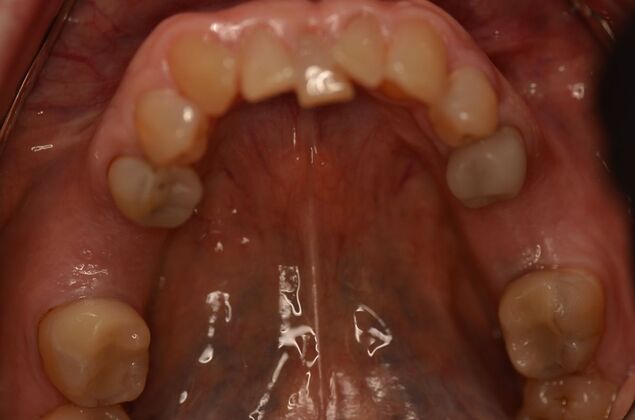

Patient lost lower first molars and required two lower implants with two lower screw retained crowns